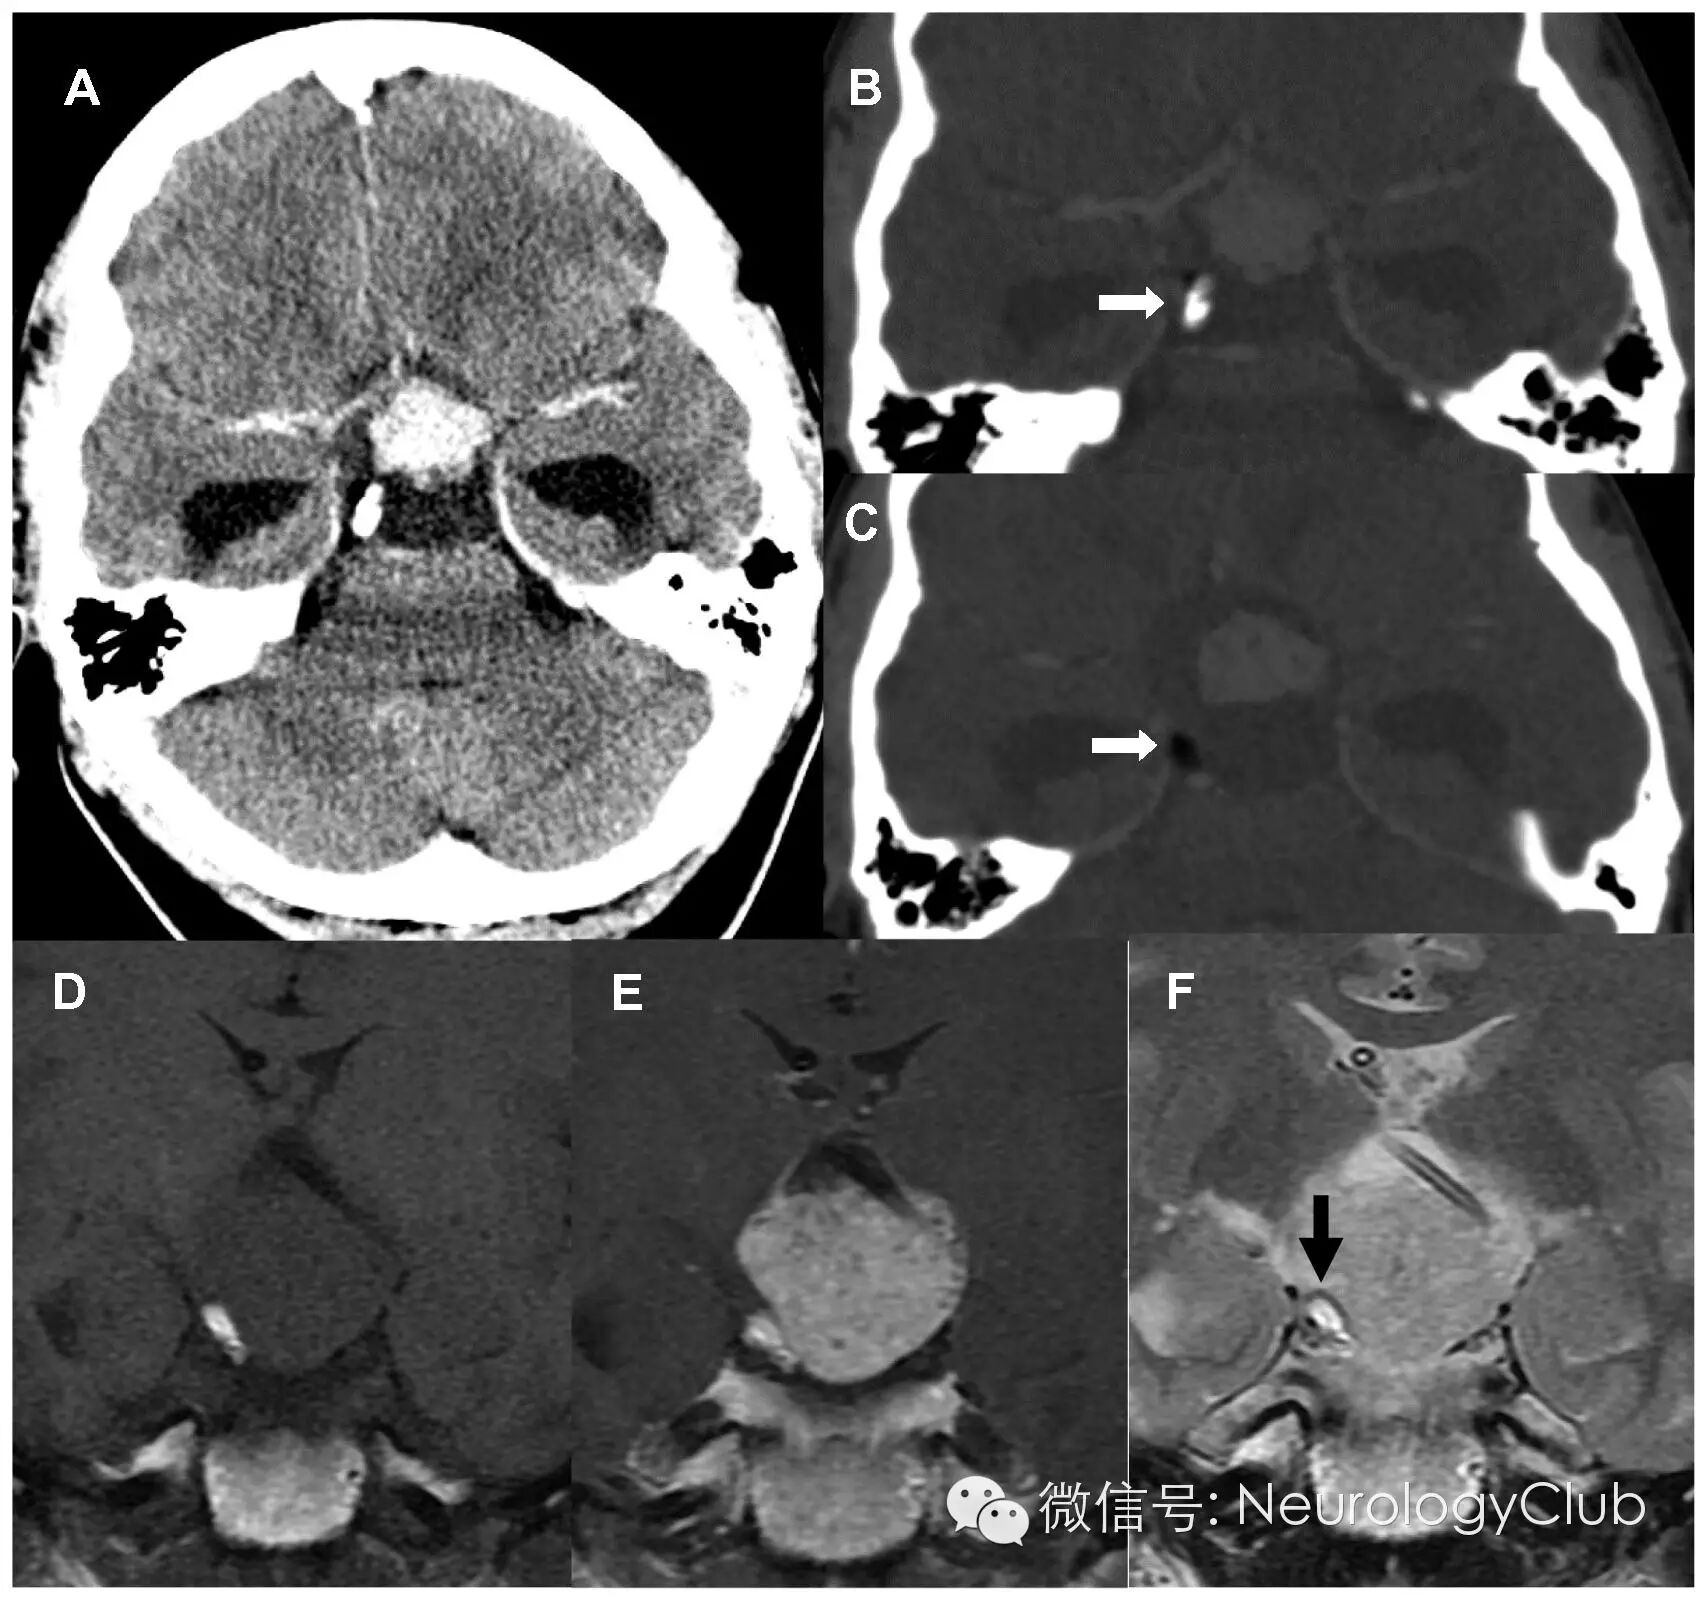

25岁白人女性,表现为头痛,困倦和凝视麻痹。既往体健。行头颅CT提示鞍上区肿块伴钙化,实性部分可强化,邻近右侧后床突可见小灶钙密度和脂肪密度影(A-C)。同时存在梗阻性脑积水。行紧急脑室分流术和肿块囊性部分分流术后,患者困倦和视觉症状有所改善。再行MR检查,提示肿块实性部分均匀强化,脂肪成分呈T1WI和T2WI高信号(D-F)。

(A-C:增强CT;D:T1WI;E:T1+C;F:T2WI)

本例患者CT上可见脂肪和骨组织,是诊断的关键。混合性囊性和实性强化肿块中同时存在上述组织,高度提示畸胎瘤的诊断,而在皮样囊肿中,强化罕见。MR进一步证实了脂肪组织的存在。病理学明确畸胎瘤的诊断。